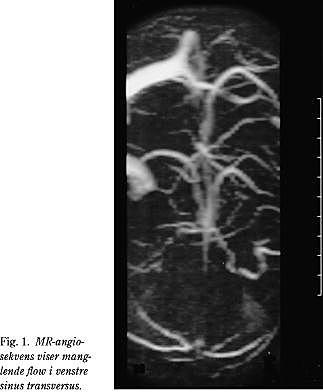

Cerebral venøs trombose er ubehandlet en farlig tilstand, der kan medføre venøse infarkter (1). Den første undersøgelse vil ofte være CT, der skal udføres både med og uden kontrast. Resultatet af CT'en kan være helt uden patologi i 10-20% af alle tilfælde (3). På de resterende scanninger ses enten direkte eller indirekte tegn på cerebral venøs trombose (1, 4). Direkte tegn omfatter bl.a. empty delta sign, hvor man ved kontrastundersøgelse ser fyldningsdefekt ved sinus, mens cord sign er hyperdense strøg fremkaldt af tromber i de kortikale vener (1, 4). Indirekte tegn på sinustrombose omfatter hjerneødem og infarkt- forandringer (1). En cerebral venøs trombose kan derfor let overses på en CT eller kan mistolkes som en anden tilstand. Diagnosen stilles hurtigt og sikkert ved MR-scanning (Fig. 1 ). Ved denne undersøgelse kan tromben erkendes visuelt direkte, ligesom man ikke invasivt kan erkende blodets strømning ved brug af MR-angiografi (1). Hvis diagnosen cerebral venøs trombose stilles, har AK-behandling med lavmolykylært heparin vist sig at bedre prognosen (5, 6). Behandlingen har også vist sig at være sikker, selv i de tilfælde, hvor der foreligger et hæmoragisk infarkt (6). Er der mistanke om en koagulationsforstyrrelse, skal der udføres en trombofilitest, hvor der undersøges for medfødte eller erhvervede defekter i koagulationssystemet (3). Cerebral venøs trombose bør altid overvejes hos en patient med uafklarede neurologiske udfald, når der samtidig foreligger en normal CT. Ved behandling er prognosen god. I et studie fra 1998 med 77 patienter fandt man god langtidsprognose, idet 85% af patienterne kom sig uden neurologiske sequelae (7). Resten fik sequelae i form af nervus opticus atrophia, symptomatisk epilepsi, hemiparese og neuropsykologiske dysfunktioner (7).